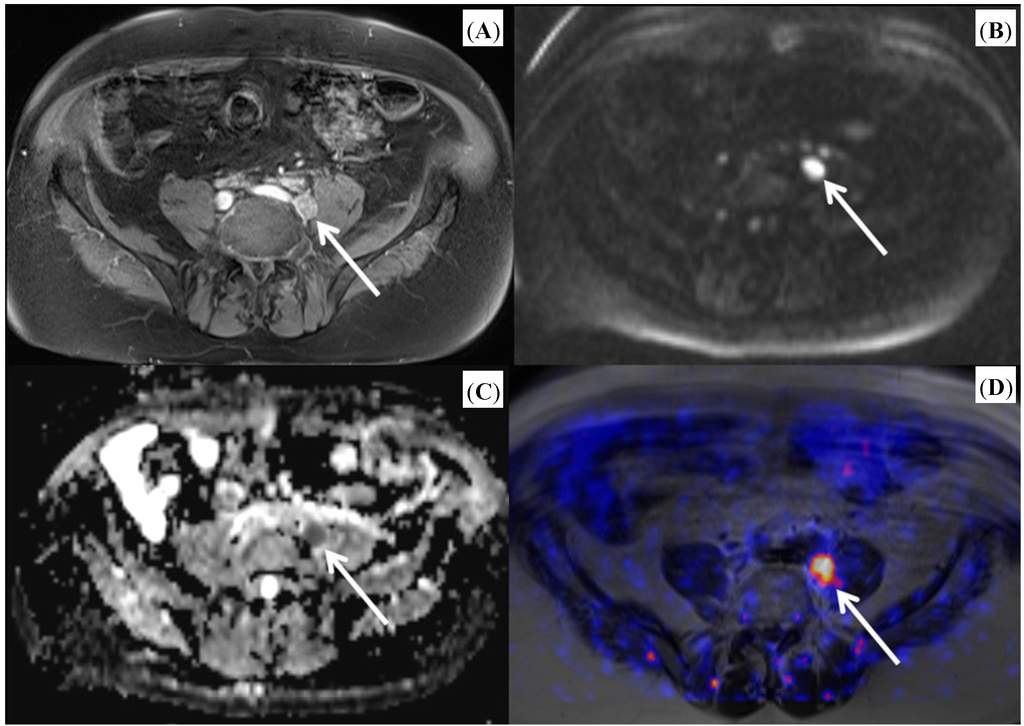

- Wetter, A.; Lipponer, C.; Nensa, F.; Beiderwellen, K.; Tobias, O.; Rubben, H.; Bockisch, A.; Schlosser, T.; Heusner, T.A.; Lauenstein, T.C. Simultaneous 18F choline positron emission tomography/magnetic resonance imaging of the prostate: Initial results. Investig. Radiol. 2013, 48, 256–262. [Google Scholar] [CrossRef]

- Wetter, A.; Lipponer, C.; Nensa, F.; Heusch, P.; Rubben, H.; Altenbernd, J.-C.; Schlosser, T.; Bockisch, A.; Poppel, T.; Lauenstein, T.; et al. Evaluation of the PET component of simultaneous [18F] choline PET/MRI in prostate cancer: Comparison with [18F] choline PET/CT. Eur. J. Nucl. Med. Mol. Imaging 2014, 41, 79–88. [Google Scholar] [CrossRef]

- Piccardo, A.; Paparo, F.; Picazzo, R.; Naseri, M.; Ricci, P.; Marziano, A.; Bacigalupo, L.; Biscaldi, E.; Rollandi, G.A.; Grillo-Ruggieri, F.; et al. Value of fused 18F-choline-PET/MRI to evaluate prostate cancer relapse in patients showing biochemical recurrence after EBRT: Preliminary results. Biomed. Res. Int. 2014, 2014, 103718. [Google Scholar]

- De Perrot, T.; Rager, O.; Scheffler, M.; Lord, M.; Pusztaszeri, M.; Iselin, C.; Ratib, O.; Vallee, J.-P. Potential of hybrid 18F-fluorcholine PET/MRI for prostate cancer imaging. Eur. J. Nucl. Med. Mol. Imaging 2014. [Google Scholar] [CrossRef]